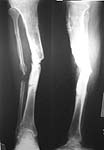

I am presenting this case for your opinion. 48 year old diabetic patient presented with 6 month old infected compound fracture right tibia with discharge of pus about two and a half years ago. He was treated earlier with external fixation, rotation flap and later with POP cast. After he presented toour unithe underwent debridement, Ilizarov ring fixation , compression at fracture site followed by distraction of upper metaphyseal corticotomy. Union was achieved in about one and a half years following which the rings were removed. He was initially given a PTB walking cast and followed by a PTB brace. He was ambulant with this.

Six months after the ring removal he fell down and refractured the original site. This was treated with POP long leg cast followed by a PTB walking cast. Now six months after the refracture, the tibia is ununited. There is no skin breakdown. Patient's present x-ray is attached.

Attaching the initial X-ray.